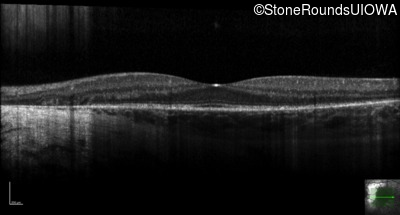

Optical Coherence Tomography - Right - 20/16

Exemplar / OCT Stack